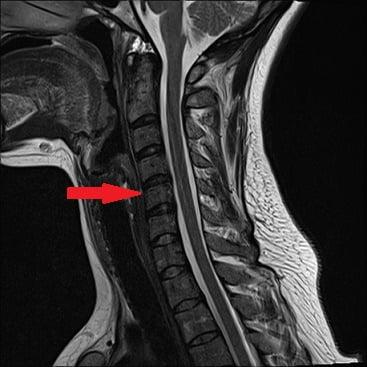

Аналогично диск л1л2 отделяет 1 и 2 позвонки поясницы, а l5s1 – 5 позвонок поясницы и 1 позвонок копчикового отдела. Есть свои обозначения и для позвонков шейного отдела – например, с5с6 отделяет 5 и 6 позвонки шеи. Однако там грыжа наблюдается реже всего ввиду небольшой нагрузки на шею, по сравнению с поясницей.

Микродискэктомия шейного отдела

Шейный отдел считается наиболее уязвимым местом на позвоночнике, ведь он густо снабжен нервно-сосудистой сетью, более того, в данной области позвоночный канал отличается большей узостью, а спинной мозг именно в верхней части позвоночника переходит в головной мозг. Выполнить микродискэктомию, о чем свидетельствуют профессиональные отзывы, в шейном отделе позвоночника посложнее будет. Но благодаря современным технологиям вместе с отменным мастерством хирурга проблем не возникнет.

Оперативный процесс протекает, так сказать, в бдительном и безопасном режиме, а это означает, что артерии и нервы не пострадают, мышцы разрезаться не будут, их только осторожно раздвинут. Основные визуализационные инструменты – микроскоп и рентген-установка. Наркоз используется преимущественно общего типа. Технически оперативный сеанс несколько отличается от того, который проводят в зоне поясницы.

- Доступ к диску осуществляется спереди, а не сзади, то есть разрез создается на передней поверхности шеи по кожной складке, а не на спине. Его величина тоже не превышает 4 см.

- Межпозвоночный диск, имеющий грыжу, на шейных участках обычно удаляют полностью, после чего между двумя позвонками располагают имплантат-стабилизатор, или кейдж. Это довольно простая в конструктивном плане система, но очень надежная.

- Кейдж поспособствует правильному сращению двух позвонковых тел воедино с сохранением биологической высоты хребта на данном участке, а также не позволит разбалансировать функциональность шейной зоны в целом.

- По времени сеанс занимает около 40-45 минут, из стационара отпускают на 3-5 сутки, а дальше пациенту нужно продолжить свое восстановление в специализированном медучреждении.

В шейном отделе позвоночника операция проводится также для того чтоб снять болевые ощущения, появившиеся из-за влияния грыжи, гипертрофированных связок или костных отростков на спинной мозг и нервные корешки.

Из-за анатомических особенностей позвоночника в области шеи, вместе с микродискэктомией может проводится стабилизирующая операция с целью прекращения трения между позвонками, которые соединяются пораженным диском, а также восстановления изначальной дистанции между ними.